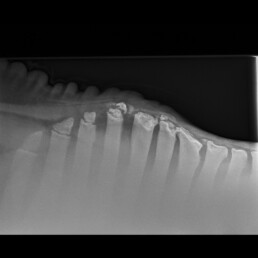

Bildgebende Untersuchung

In der röntgenologischen Untersuchung des Widerristes wurde im Bereich der Tuberositas processus spinosi der Knorpelkappe des T5 ein geringgradig disloziertes Frakturfragment geringer Größe festgestellt (Abb. 6). Ein weiteres Frakturfragment geringer Größe und ohne Dislokation wurde im Bereich der Knorpelkappe des T7 dargestellt. Die Tuberositates processi spinosi der Wirbel T6 und T8 zeigten reaktive Konturveränderungen. In der Unterhaut stellte sich eine Verschattung im Bereich des Narbenzuges dar.

Abb. 6

deutliche Verschattung in der Unterhaut